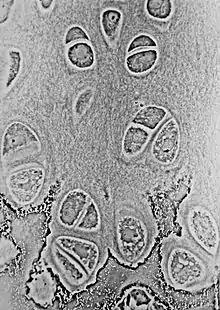

Cartilajul hialin la microscop

Cartilajul alcătuiește țesutul cartilaginos, care poate fi de mai multe tipuri: hialin, elastic și fibros. [2]